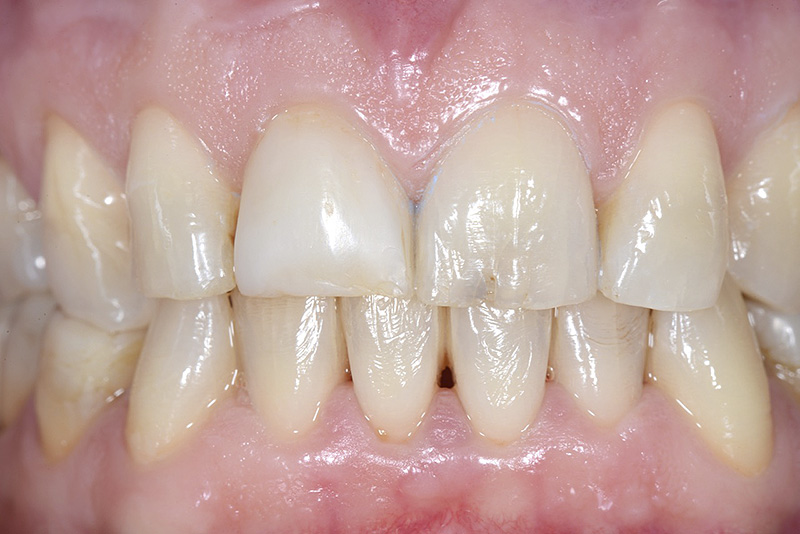

PREMESSA: in seguito all’estrazione dell’incisivo laterale superiore di destra, resasi necessaria per cause batteriche, si decide di affrontare il caso con il posizionamento di un impianto in sostituzione dell’elemento mancante dopo guarigione del sito infetto. Con tecniche rigenerative sia dei tessuti ossei mancanti a causa dell’infezione pregressa, sia dei tessuti gengivali che appaiono inizialmente troppo spostati in alto, si ripristina una corretta morfologia delle parabole (contorni) gengivali e delle papille interdentali (triangoli di gengiva tra due denti vicini).

Vengono utilizzati 2 tipi di provvisori: il primo, cementato ai denti vicini, viene utilizzato dal momento dell’estrazione del dente fino ad impianto osteointegrato (circa 6 mesi); il secondo, avvitato direttamente all’impianto, ha una funzione di prova estetica ma soprattutto di guida per la maturazione dei tessuti gengivali peri-implantari portandoli verso la maturazione completa prima di posizionare la corona finale in disilicato di litio.